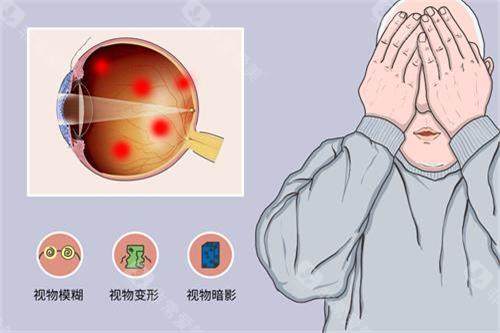

眼底病与眼外伤专科:显微手术的"艺术"

余锦强医师是玻璃体视网膜疾病领域的显要,尤其擅长复杂性视网膜脱离、糖尿病视网膜病变的小创口玻切手术,手术精细度高,视功能重建改善显著。华远锋副高医师则在眼外伤急诊处理方面技术娴熟,能够及时救治眼球破裂伤等急症,更大限度保留患者眼球结构和功能。

急诊优势:科室设有24小时眼外伤绿色通道,配备全视网膜镜辅助下的玻璃体视网膜显微手术系统,确保急症患者得到及时救治。